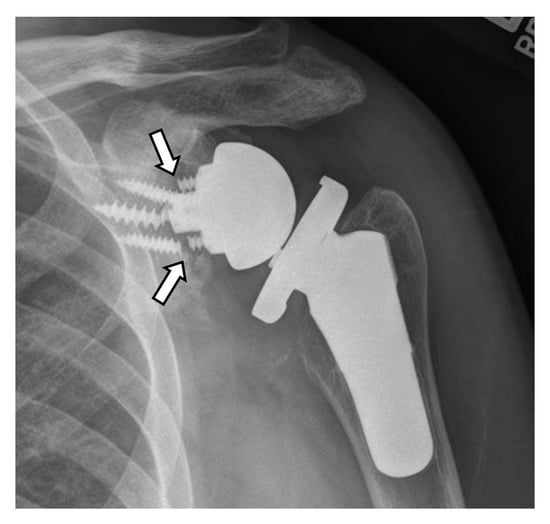

4.2.1. Loosening and Hardware Dissociation

5.2. Reverse Arthroplasty

Reverse Total Shoulder Arthroplasty (RTSA)